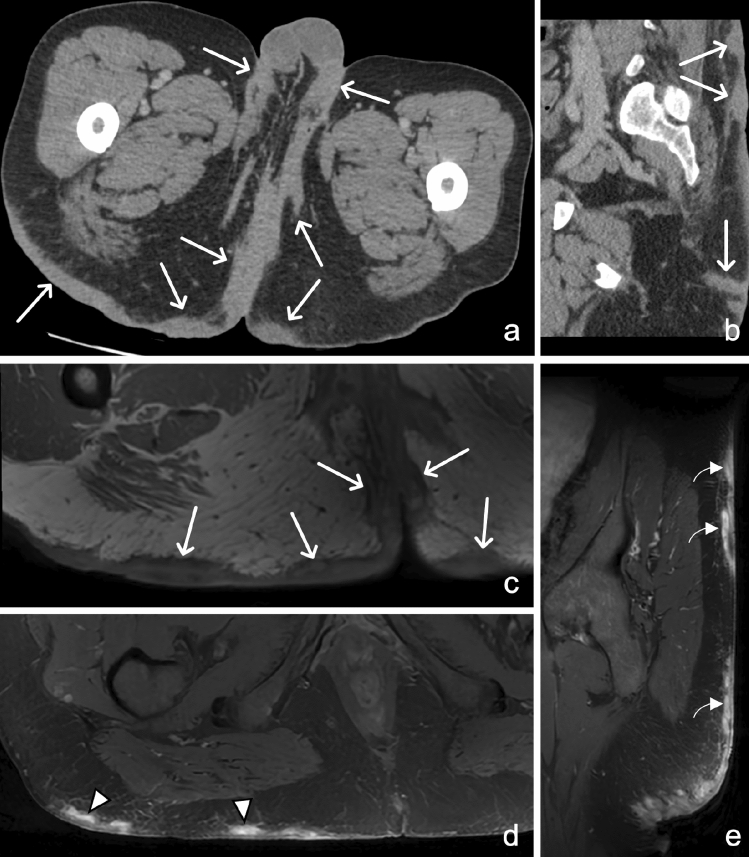

Fig. 21.

30-year-old male with Hidradenitis Suppurativa (HS). Axial (a, b) and coronal (c) CT reformats through the gluteal cleft and perineum demonstrate nodular, bilateral, fairly symmetrical subcutaneous soft tissue thickening (arrows) with sinus track formation (arrowhead) in a patient with pathologically proven HS. Contrast these findings with a different patient with cellulitis. Axial (d) CT image illustrates diffuse “fat stranding” in the left greater than right gluteal subcutaneous soft tissues (curved arrows), compatible with cellulitis. A developing fluid collection is noted in the right gluteal subcutaneous tissues

Fig. 22.

49-year-old male with Hidradenitis Suppurativa (HS). Axial CT (a), sagittal CT (b), axial T1W (c), axial T2 fat-saturated (d), and sagittal post-contrast fat-saturated T1W (e) MR sequences demonstrate diffuse nodular skin thickening (arrows) along the scrotum, bilateral groin, medial thighs, posterior buttocks, and lower back with linear high T2 signal suggestive of sinus tracks (arrowheads) and areas of superimposed enhancement which may represent superimposed infection or micro abscesses (curved arrows)